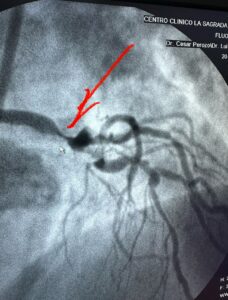

Álvaro Yépez, de 67 años, enfrenta una situación crítica de salud, tras ser diagnosticado con síndrome coronario crónico (SCC), con una lesión ateromatosa oclusiva crítica del 99 % en el tercio distal del tronco de la coronaria izquierda.